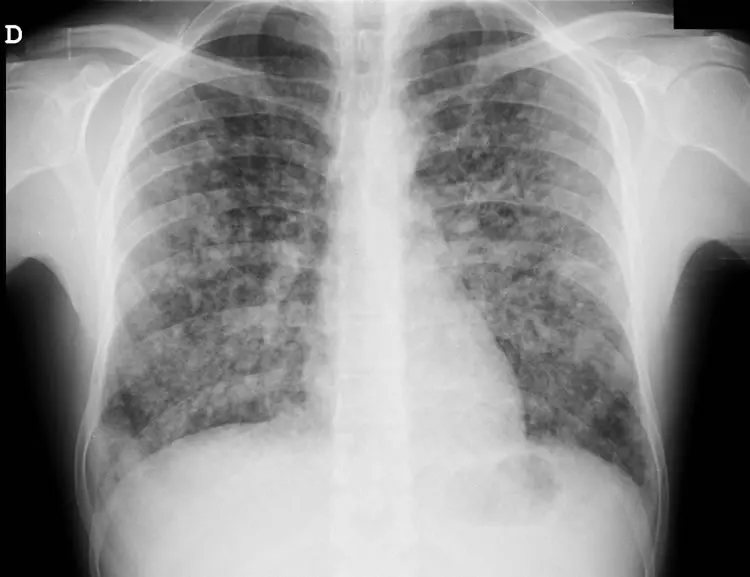

Quais os achados radiológicos mais comuns na pneumonia comunitária?

Infiltrado pulmonar do tipo alveolar broncopneumônico com presença de broncograma aéreo